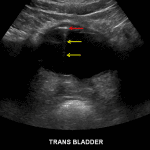

Ultrasound